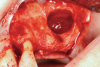

Fig 15. In a separate case, prepared L-PRF for use as a biologic bandage at palatal donor site after FGG harvest is shown (Fig 15); intraoperative photograph (Fig 16) shows L-PRF membrane sutured at palatal wound site after FGG harvest for postoperative pain control.

Figure 15